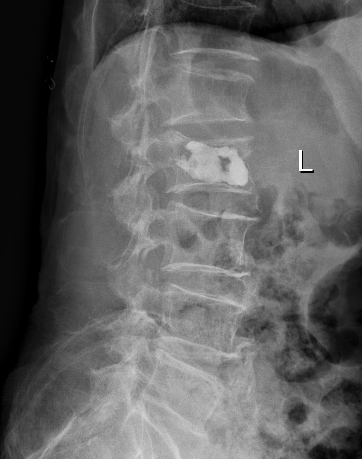

十余年来,我科室相继开展骨质疏松症的相关诊治工作,逐渐形成了自身的诊治体系,后经过整合联系,形成了以骨科二病区为龙头,联合检验科、放射科、内分泌科、血液风湿科等多学科结合、内外协作的骨松诊治MDT模式。目前采用的诊断方式有血钙及维生素ADKE检测、双能X线骨密度检测等,治疗方面也内外兼修,既可应用促成骨的四烯甲萘醌等,抑制骨吸收的唑来膦酸等药物治疗,又可采取椎体强化术、经皮穿刺椎弓根钉置入术等有效手术治疗,可结合患者自身情况,采取合适的治疗手段。开展骨质疏松诊治工作的十几年来,遵循指南,结合当地实际,总结归纳出了一套立足自身实际的诊疗体系,采取药物治疗与手术治疗相结合、因人而宜、综合施治的个体化的综合诊疗方案等。近年来,随着微创理念的推行和ERAS理念的实践,骨科二病区率先在本地区开创性的应用微创经椎间孔入路椎体强化术、经皮穿刺椎弓根钉置入术等先进治疗手段,实现立竿见影的治疗效果,深得广大患者的好评,取得了良好的社会效益和学术影响力,使桓台百姓足不出县即可享受到国内外先进的脊柱外科诊治体验。

术后术前